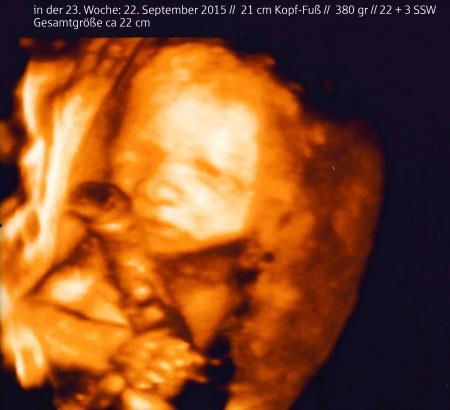

Es gab sogar ein 3D-US-Bild. Unglaublich wie präzise das alles ist.

Hello Juleika ... echt?? WIE toll. Auf Video sowas festzuhalten muss echt klasse sein! Ich hab "leider" ne Vorderwandplatzenta. Da sieht man erst ganz spät was von außen. Fühlen kann ich meinen Copiloten aber abends immer ... schon seit der 16. SSW und auch tagsüber zwischendurch. Besonders lustig, wenn ich in ner Besprechung sitze und nur zuhöre und der Meister da drinnen anfängt rumzuturnen!!! So sitz ich wenigstens IMMER mit nem Grinsen im Gesicht da! Das Bild hab ich jetzt mal "neutralisiert" unfassbar gute Aufnahme ... das "Braune" was er umklappert ist die Nabelschnur.

Wow, tolles Bild.